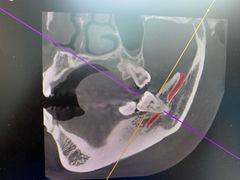

• 牙博士口腔品牌连锁(杨浦店)

• -牙博士口腔品牌连锁(杨浦店)

tomy_jun | 24-06-30

报错